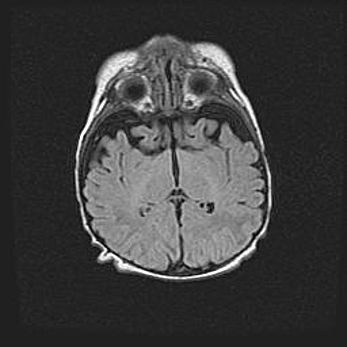

Церебральная ишемия II.

Возраст: 5 дней

Вес: 3400 г

Пол: женский

Окружность головы: 35 см

Срок гестации: 39 недель

Церебральная ишемия – это заболевание, характеризующееся недостаточностью (гипоксией) либо полным прекращением (аноксией) снабжения мозга кислородом по причине закупорки одного или нескольких сосудов. Это приводит к  что метаболическим расстройствам различной степени тяжести в тканях головного мозга, развитию коагуляционных некрозов и гибели нейронов.